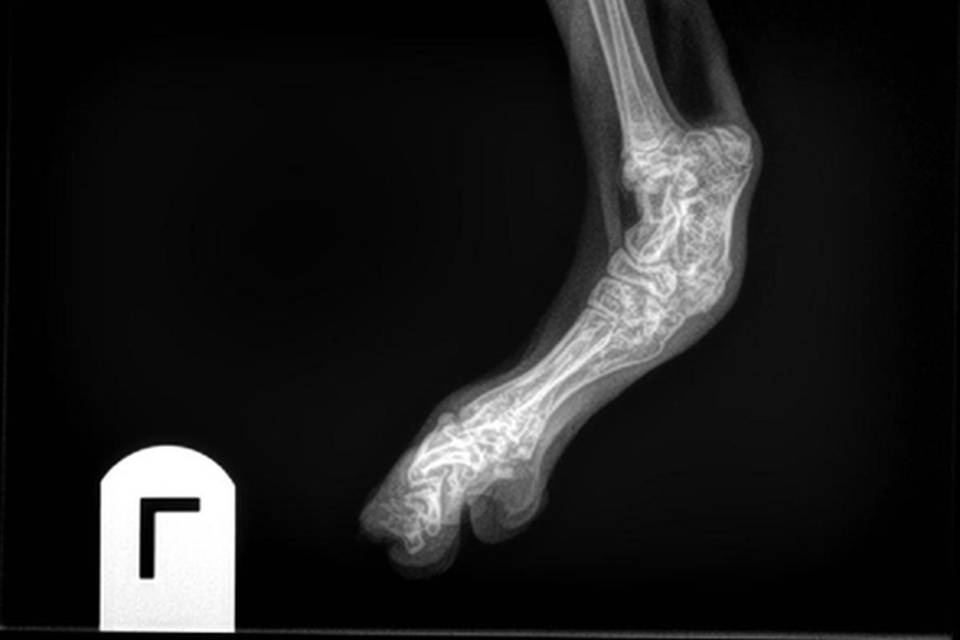

SFO is een erfelijke aandoening die voorkomt bij de Scottish Fold. Door deze afwijking zal het kraakbeen niet normaal volgroeien en functioneren. Hierdoor ontstaat ernstige artrose. Dit kan al op jonge leeftijd zichtbaar zijn en leidt ertoe dat aangetaste dieren mank en stijf gaan lopen en minder of niet willen springen.

De diagnose kan bevestigd worden door het maken van röntgenfoto's.